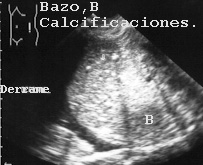

La autopsia no la encontró porque quedó oculta en el interior de las secciones macroscópicas del hígado, por lo que concluyó que solo había diseminación a ganglios linfáticos regionales del carcinoma de colon que era la enfermedad fundamental del paciente. Análogamente no fueron encontrados en la autopsia granulomas calcificados hepáticos y esplénicos en un paciente con historia de tuberculosis miliar (Fig 12).En la imagen se observan como nódulos redondos, hiperecogénicos (blanquecinos),

12BAZOCA.JPG (16342 bytes)

Fig 12